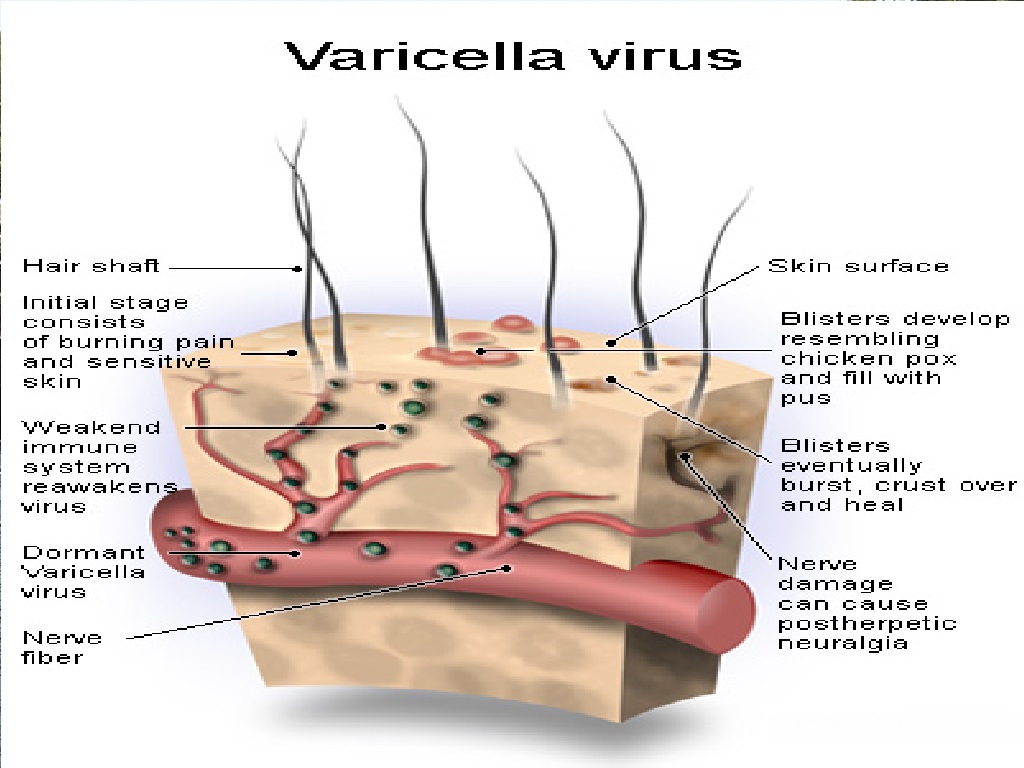

Медицинские снимки и изображения опоясывающего герпес вируса

Раздел: Фотодневник открытий